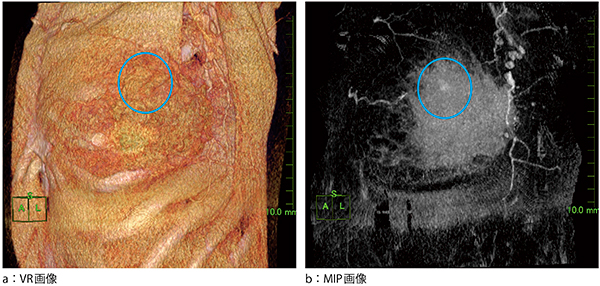

症例2も浸潤性乳管がんの症例であるが,こちらの症例では腫瘍の濃染が強くないためVR画像(図3 a)では認識できない。しかし,MIP画像(図3 b)を用いることにより一目で確認することが可能である。

図3 症例2:浸潤性乳管がん

VR画像では,周囲組織に埋もれてしまい淡い染まりが見にくいが,MIP画像では一目で認識可能である。